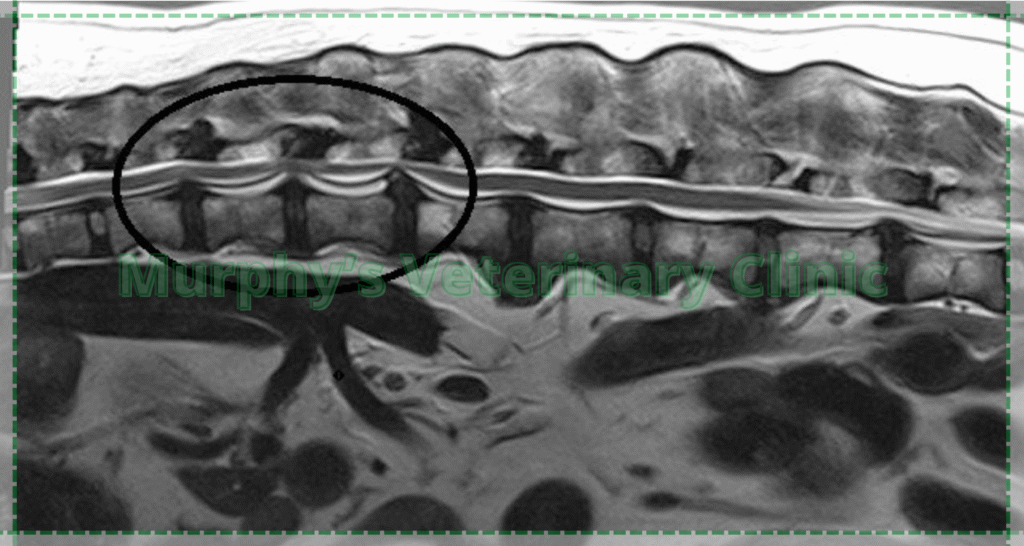

Diagnosing Intervertebral Disc Disease requires not only a thorough clinical examination but also the integration of advanced diagnostic imaging techniques such as MRI, CT scans, and specialized radiography. Veterinarians rely on a wide range of clinical tools to carefully assess the spinal condition, evaluate neurological function, and accurately localize the specific site of the lesion along the spine. By combining these methods, they are able to form a precise understanding of the severity of the disease and develop an appropriate treatment plan tailored to the individual animal. Early detection plays a crucial role in the overall management of the disorder, as identifying the condition in its initial stages allows for less invasive treatment options, reduces the risk of permanent damage, and significantly improves the likelihood of a successful recovery and restoration of mobility.

- Magnetic Resonance Imaging (MRI)